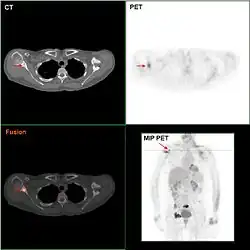

- Obrazowanie metodami nuklearnymi (scyntymammografia, Miraluma test): guzy nowotworowe pochłaniają zwiększone ilości promieniotwórczego izotopu technetu (sestamibi Tc-99), co można zobrazować zliczając zmiany lokalnej emisji promieniowania. Dość dobra czułość występuje tu przy niskej rozdzielczości obrazu; dawka promieniowania jest jednak większa niż przy mammografii[194][147].

- Emisyjna tomografia pozytonowa (PET): budzi podobne zastrzeżenia jak techniki nuklearne[194].